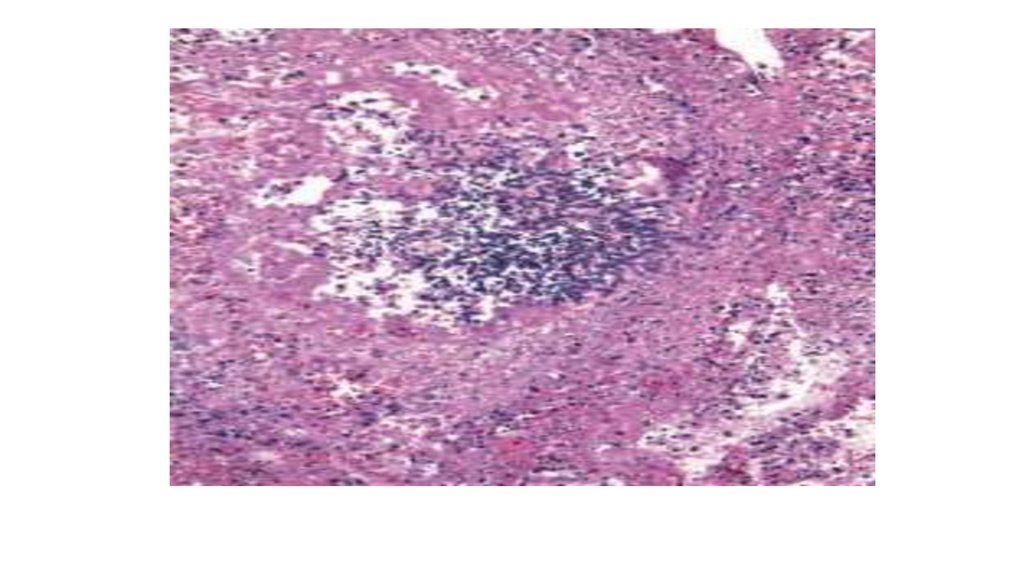

Қызылша кезіндегі пневмония: серозды макрофагальды-десквамативті

пневмония интерстициальды компонентпен, перибронхиальды тін зақымдалуы